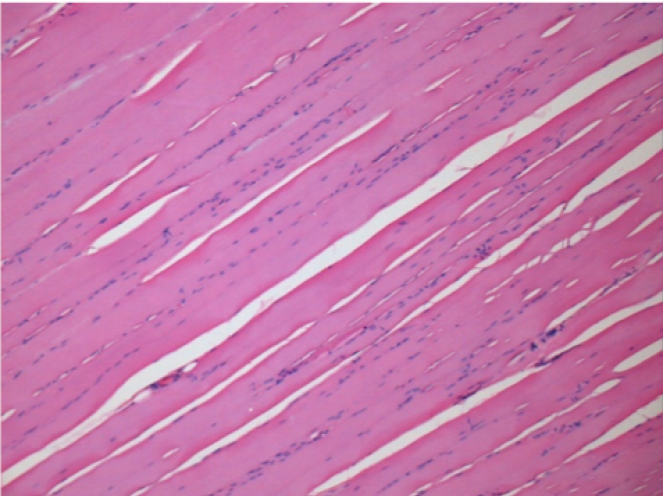

1 month after Endopeel Injection 0.1ml in the right pretibial muscle.

What is seen in black on the pictures is not a necrosis like could imagine some scientifics !

In fact, 4 conclusions have to be taken in consideration